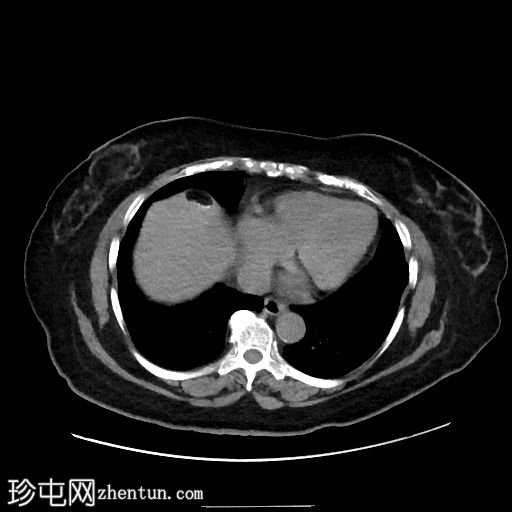

1.jpg

轴位

平扫

肝脏VIII段可见边界清晰的含液和脂肪的病变,边缘可见钙化,符合卵巢畸胎瘤肝包膜沉积。